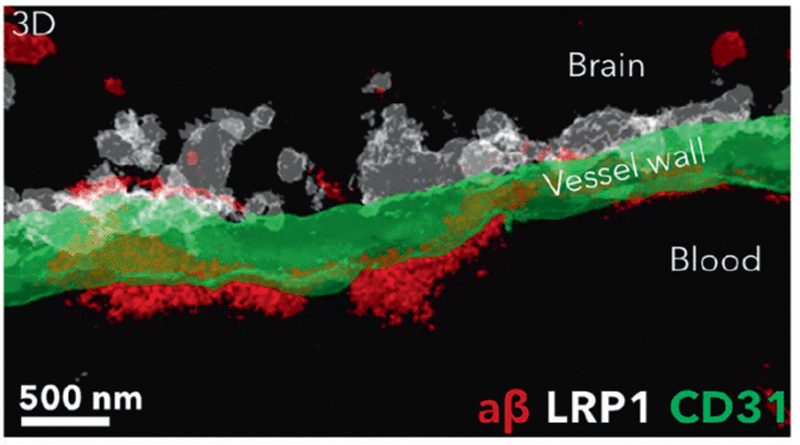

اما بهگفته نویسندگان اصلی پژوهش، جونیانگ چن و پان شیانگ از دانشگاه سیچوان و همکارانشان، این رویکردها سد خونی-مغزی را صرفاً دری برای عبور، و نه بافتی معیوب برای ترمیم، در نظر میگیرند. در مقابل، پژوهشگران در چین و اسپانیا بهجای تلاش برای وارد کردن دارو به مغز، در پی آن هستند که خروج آمیلوئید بتا از مغز را تسهیل کنند.

رویکرد نوآورانه این پژوهش از فرضیهای نوظهور پشتیبانی میکند که بر اساس آن، سد خونی-مغزی در بیماران آلزایمری تضعیف یا دچار اختلال میشود و همین امر موجب تجمع مواد زائد در مغز میگردد.

به گفته تیم بینالمللی پژوهشگران، در بیماری آلزایمر، مشکل تنها محدود به دسترسی نیست؛ بلکه خود سامانهی انتقال در مغز نیز بهطور بیماریزا دچار اختلال عملکرد شده است. دانشمندان در این مطالعه از نانوذرات نه بهعنوان حاملهای غیرفعال دارو، بلکه بهعنوان عوامل فعال تغییر استفاده کردند و از این طریق توانستند جریان عبور مواد از سد خونی-مغزی را اصلاح کرده و فرآیند پاکسازی پلاکهای آمیلوئیدی را در مغز موشها بازگردانند.

به گفته پژوهشگران، نانوذرات مانند مهندسان ریزمقیاس رفتار سلولی عمل میکنند و فرآیند ترمیم را در سطح مولکولی هدایت مینمایند. هدف نهایی آنها پروتئینی به نام LRP1 اندوتلیال است که در حذف پلاکهای آمیلوئید بتا در ناحیه سد خونی-مغزی نقش دارد.

جوزپه باتالیا، مهندس زیستی از مؤسسه مهندسی زیستی کاتالونیا (IBEC)، توضیح میدهد: «تأثیر بلندمدت این روش از طریق بازسازی رگهای خونی مغز حاصل میشود. تصور ما این است که این روند مانند یک زنجیره عمل میکند: زمانی که مواد سمی مانند آمیلوئید بتا تجمع مییابند، بیماری پیشرفت میکند. اما هنگامی که سیستم عروقی دوباره توان عملکرد طبیعی خود را به دست آورد، شروع به پاکسازی آمیلوئید بتا و دیگر مولکولهای مضر میکند و در نتیجه کل سامانه به تعادل بازمیگردد.»

او میافزاید: «نکته چشمگیر اینجاست که نانوذرات ما خود بهعنوان دارو عمل میکنند و بهنظر میرسد یک سازوکار بازخوردی را فعال میسازند که مسیر پاکسازی را به سطح طبیعی بازمیگرداند.»